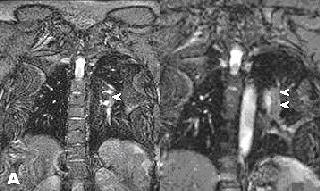

![]() |

| Above, contrast-enhanced renal MRA on a Magnetom Avanto scanner. Imaging protocol included 3D FLASH with TR/TE 2.5/1/1 msec in 20 seconds. Below, 3D TrueFISP fat-saturated navigator-gated noncontrast renal MRA. Time: Five minutes. TR/TE 900/1.6 msec. Inversion time 600 msec (work-in-progress). Images courtesy of Siemens Medical Solutions USA. |